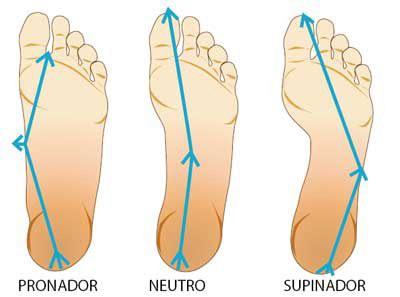

Tale considerazione ci sarà utile per spiegare, in seguito, il meccanismo di insorgenza dell’impingment posteriore. Il cosiddetto “collo del piede” corrisponde, anatomicamente, alle porzioni del tarso e dei metatarsi: la maggiore o minore mobilità di queste componenti scheletriche dipende da innumerevoli fattori quali il tipo di piede (normale, cavo, piatto), dalla lassità capsulo-legamentosa delle strutture interessate, ma anche da un corretto uso della muscolatura.